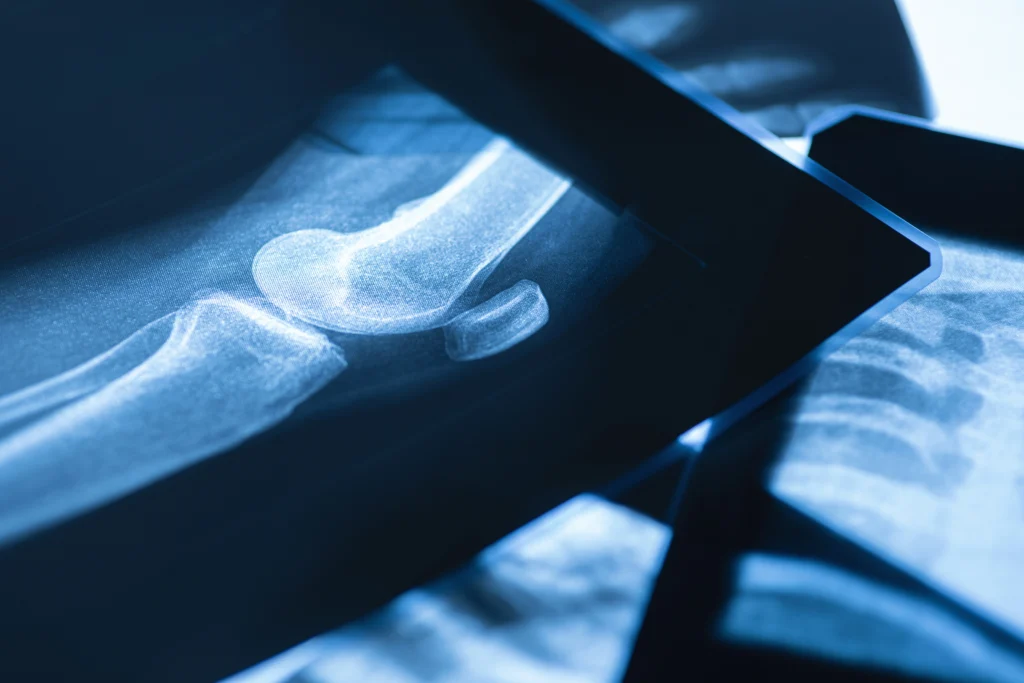

Az ízület alapvető szerkezeti elemei

Az ízület több, egymással szoros kapcsolatban álló struktúrából épül fel. Az ízfelszíneket borító ízületi porc biztosítja a csontvégek súrlódásmentes elmozdulását és a terhelés egyenletes eloszlását. A porcfelszínt az ízületi tok veszi körül, amely mechanikai védelmet nyújt és stabilizálja az ízületet. Az ízületi tok belső felszínét az ízületi belhártya borítja, amely az ízületi folyadék termeléséért felelős. Ez a folyadék látja el a porcot tápanyagokkal, mivel az ízületi porc saját vérellátással nem rendelkezik.

Az ízületi porc szerepe és sérülékenysége

Az ízületi porc különösen ellenálló, ugyanakkor rendkívül érzékeny szövet. Feladata a terhelés csillapítása és az ízfelszínek védelme. Kopás, túlterhelés, sérülés vagy gyulladás hatására azonban szerkezete fokozatosan károsodhat. Mivel a porc anyagcseréje lassú, regenerációs képessége korlátozott. Ezért kiemelten fontos minden olyan folyamat támogatása, amely javítja a környező szövetek keringését és az ízületi folyadék minőségét.